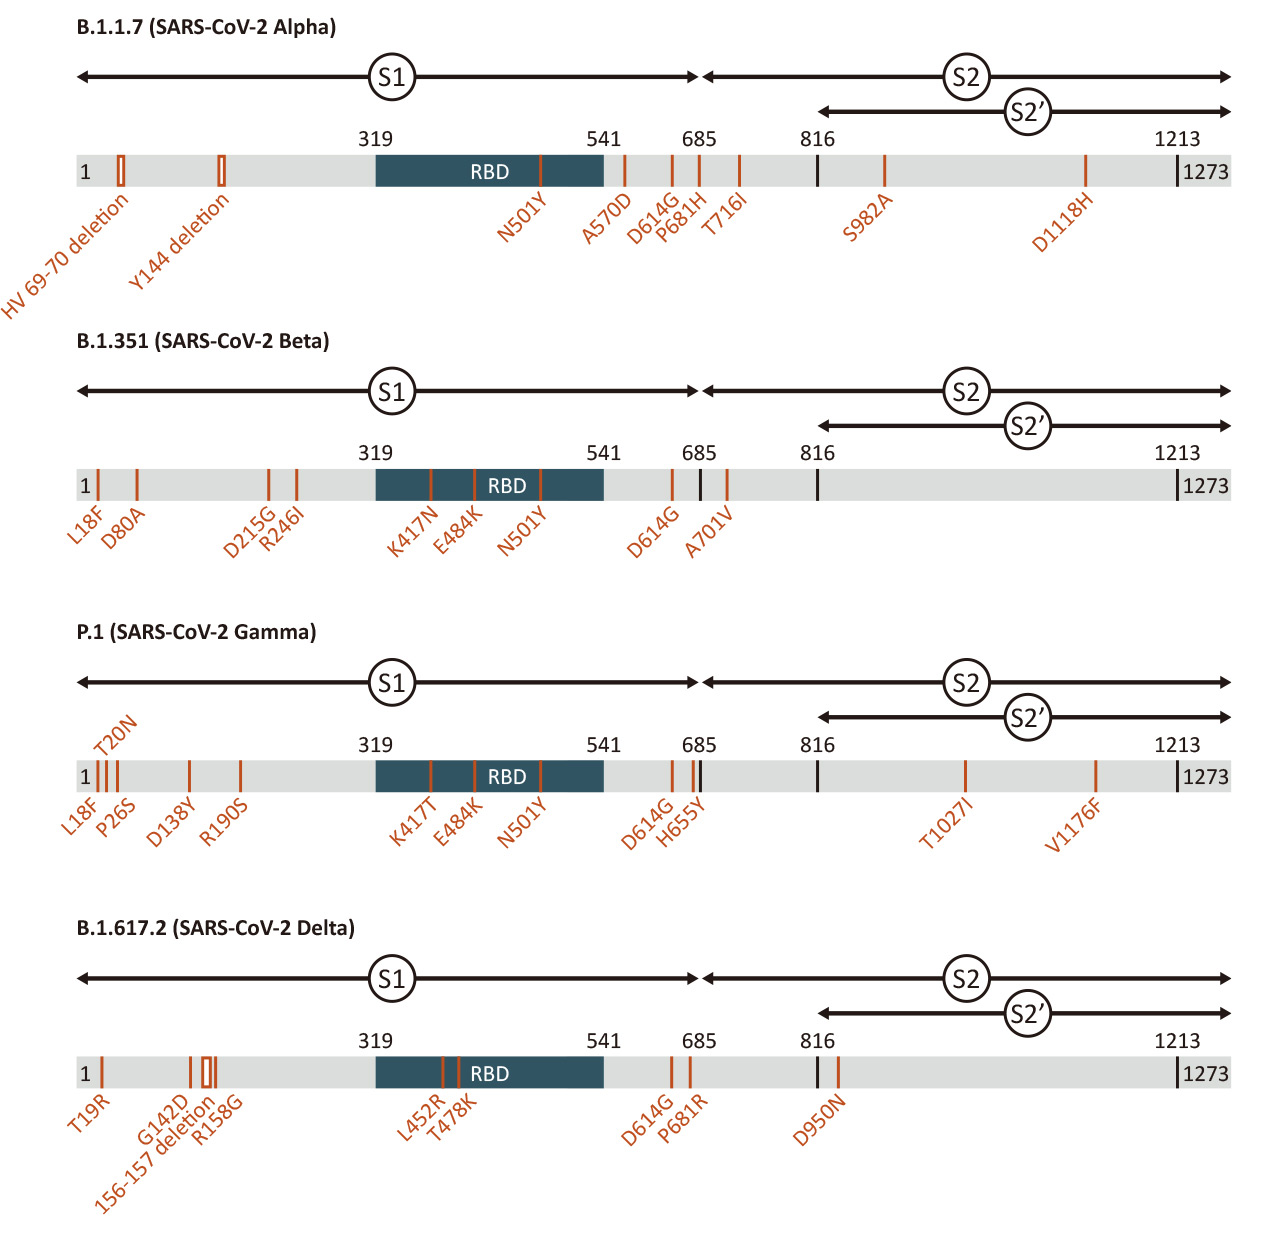

| Spike (S) | Spike full-length (~1273 a.a. in SARS-CoV-2) protein precursor is cleaved into glycosylated subunits, S1 and S2 (S2’). S1 binds to the host’s receptor, ACE2, while S2 mediates viral and host membrane fusion. | 1 |